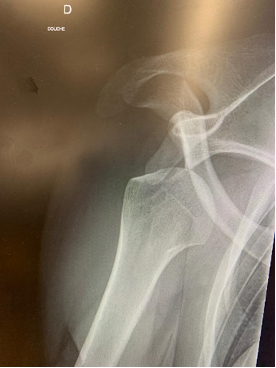

Ces radiographies mettent en évidence une luxation antérieure de l’épaule avant et après réduction.Lors d’une luxation de l’épaule plusieurs étapes sont nécessaire :

1. Effectuer une radiographie afin de confirmer le diagnostic et de vérifier l’absence de fracture sous-jacente.